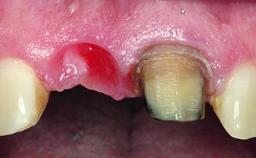

Replacement of a Compromised Upper Right Central Incisor: Hard- and Soft-tissue Augmentation, Late Placement of an RC Bone Level Implant

A 36-year-old male patient with a compromised maxillary central incisor was referred by his general dentist for consultation. The patient’s chief complaints were the gradual debonding of a temporary crown on the right central incisor and unsatisfactory esthetics due to an increasing diastema between the right central and lateral incisors. The patient reported a traumatic event some years previously, when a crown had been placed after root-canal treatment. The referring dentist wanted to provide a new crown restoration, but was concerned about the condition of the residual root. Anamnesis was negative for any other dental or periodontal pathology in the remaining dentition. The patient reported taking no medications: He was a smoker (10 to 15 cigs/day) and had realistic esthetic expectations.

Soft Tissue Grafting Simultaneous

Soft Tissue Anatomy Intact Defective

Soft Tissue Contour and Volume Slightly compromised